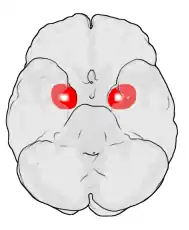

Миндалевидное тело (лат. corpus amygdaloideum), ами́гдала[1] — область мозга миндалевидной формы, находящаяся в белом веществе височной доли полушария под скорлупой, примерно на 1,5—2,0 см сзади от височного полюса. В мозге два миндалевидных тела — по одному в каждом полушарии[2]. Миндалевидное тело играет ключевую роль в формировании эмоций, в частности, страха. У пациента, миндалевидное тело которого оказалось полностью разрушено вследствие болезни Урбаха — Вите, наблюдалось отсутствие страха[3][4][5]. Миндалевидное тело также играет важную роль в функционировании памяти, принятии решений и эмоциональных реакциях[6]. Миндалевидное тело является частью лимбической системы, относится к подкорковым обонятельным центрам.